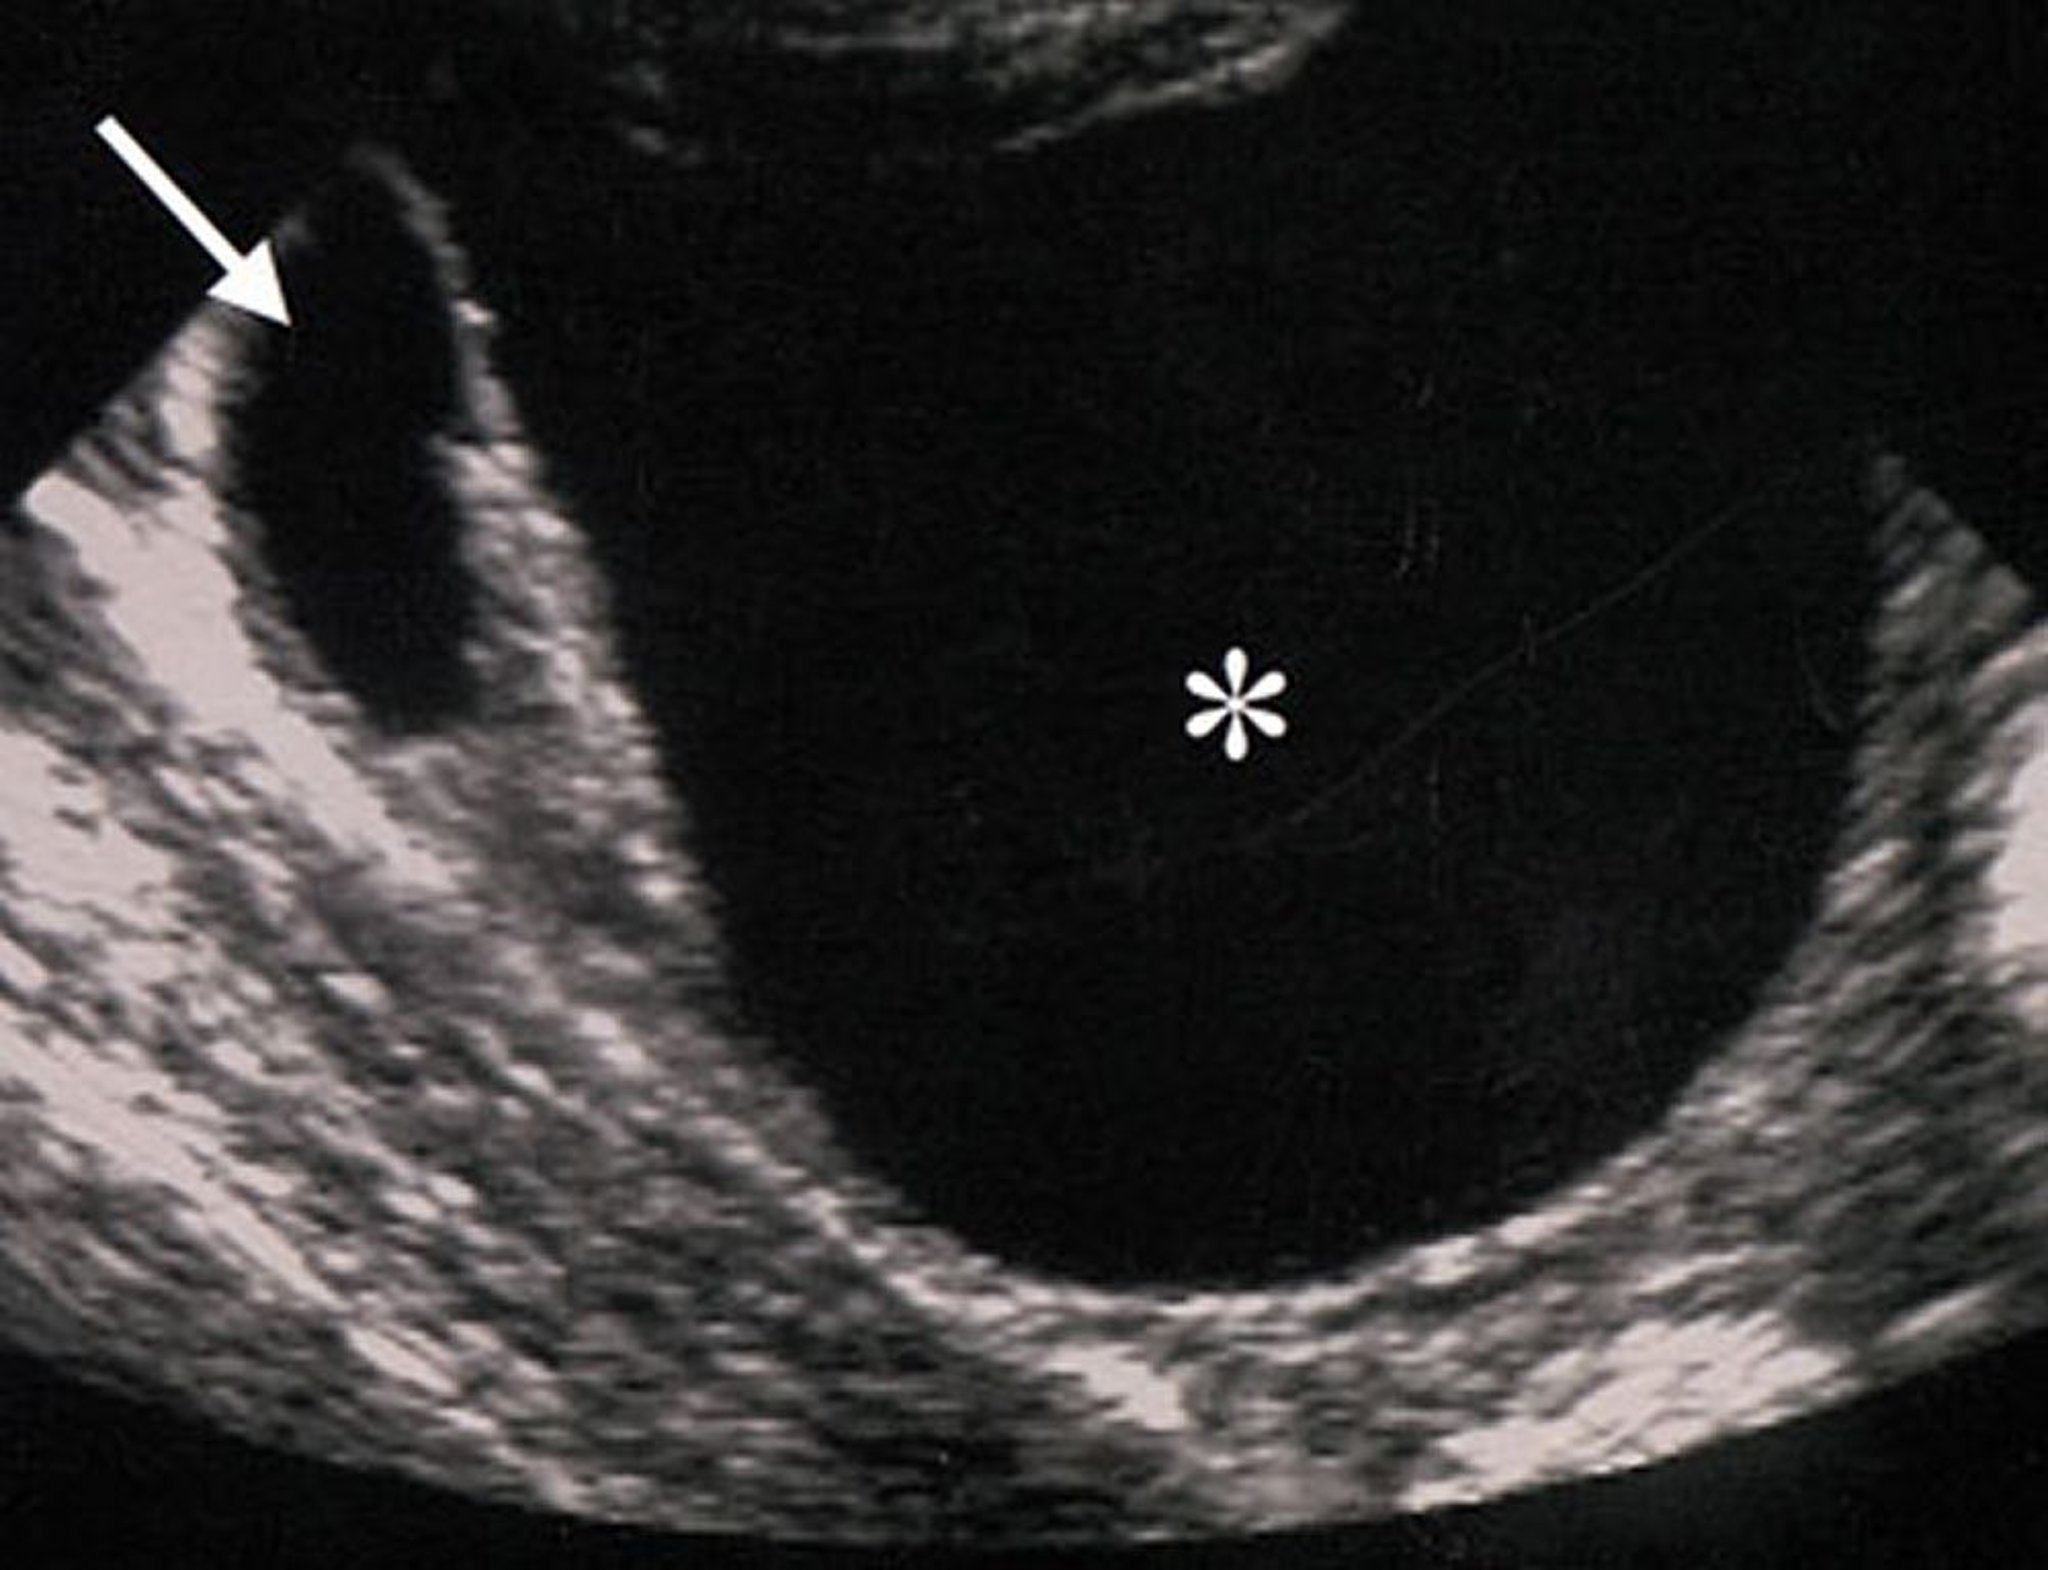

良性卵巣腫瘤の超音波所見

この卵巣腫瘤の超音波上の特徴(アスタリスクで示す)は,腫瘤が良性であることを示唆している。腫瘤は無エコー性(充実性成分が存在しないことを示す),整,境界明瞭で,壁の肥厚や突出物を伴わない。